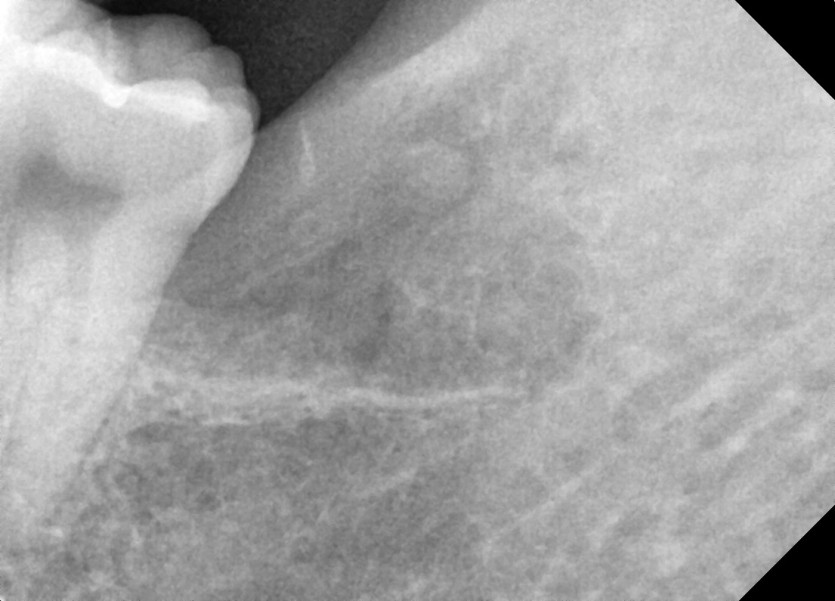

#28,38 사랑니 발치

구강 외과 전문의가 당일 발치했습니다.